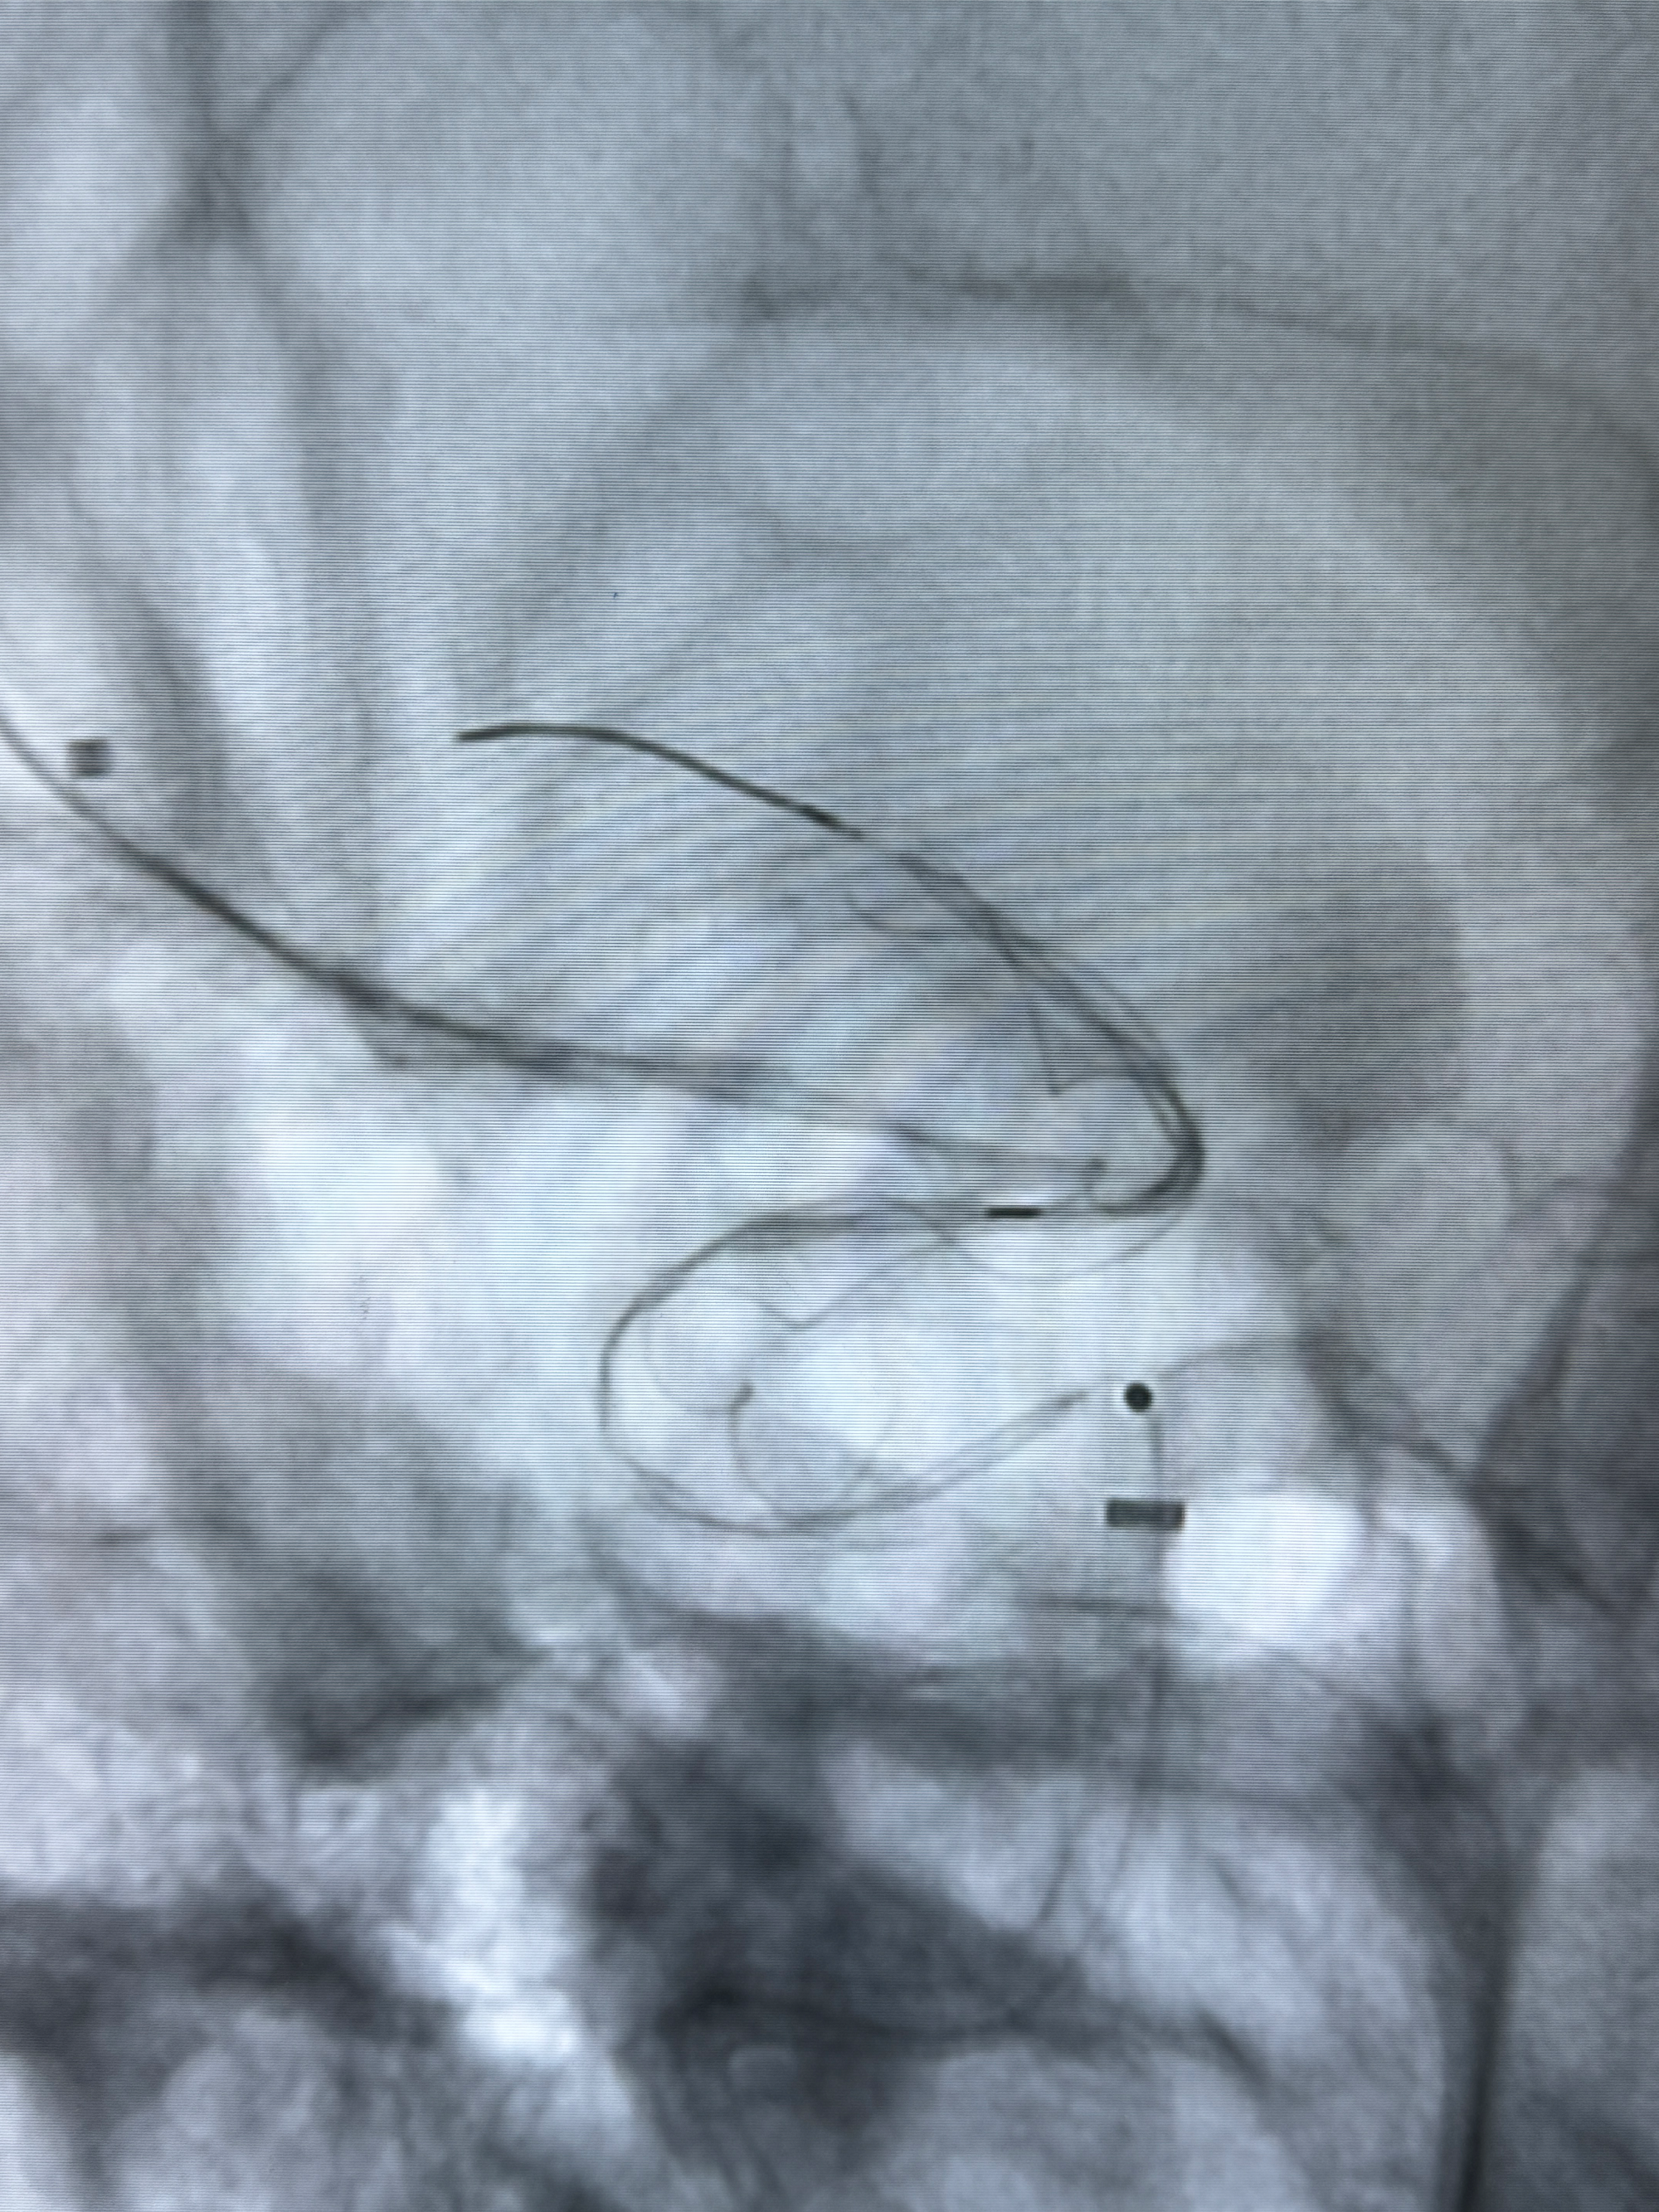

手术开始了,088导管在MPA及泥鳅导丝引导下进入右侧颈内动脉,灌注盐酸法舒地尔5mg

造影见血管痉挛改变,再灌注盐酸法舒地尔5mg

密网支架微导管在微导丝引导下超选择性插入右侧大脑中动脉

越慢越快,越快越慢:耐心细致的操作是顺利的保障

切换到动脉瘤瘤颈的角度,栓塞导管塑形后引入动脉瘤内